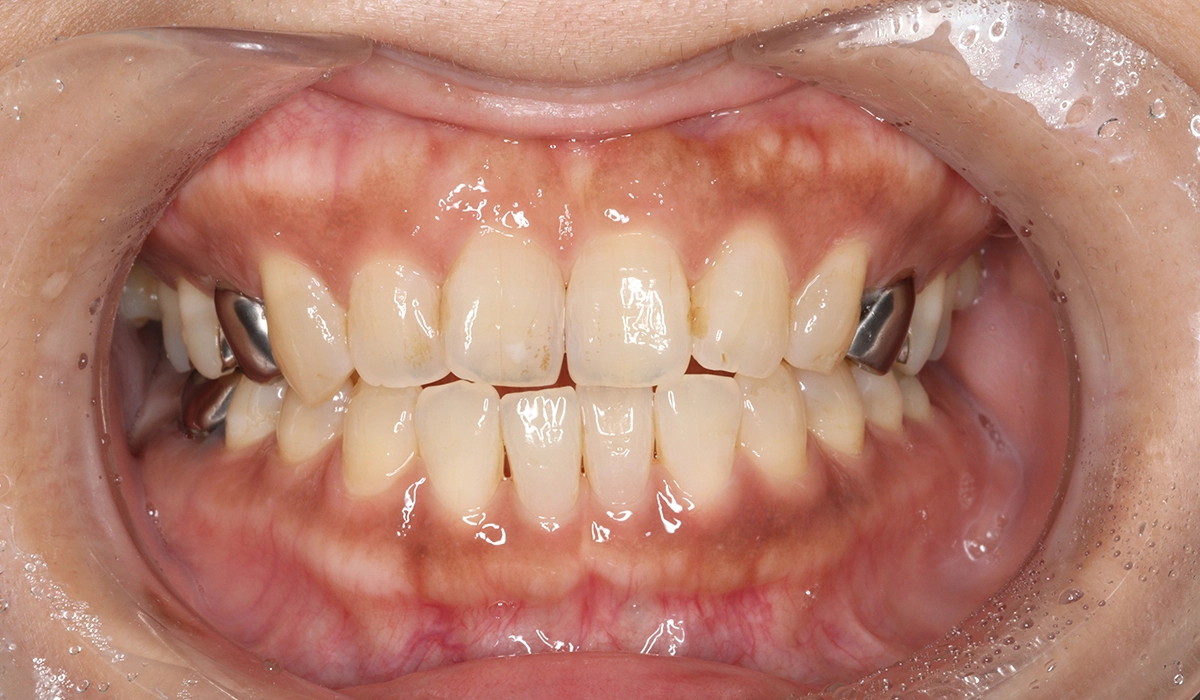

術後:正面